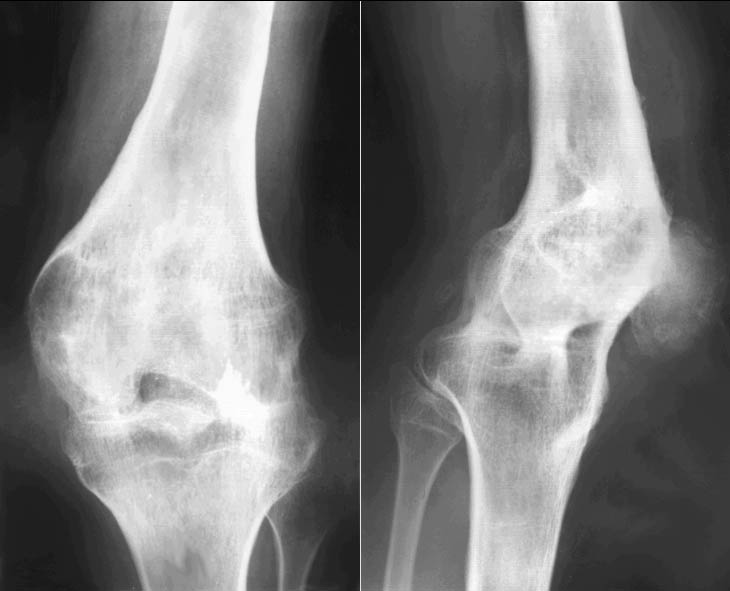

Для диагностики гонартроза применяются рентгенография коленного сустава и лабораторные анализы крови. Увеличение скорости оседания эритроцитов (СОЭ) указывает на воспалительный процесс в организме. Рентгеновские снимки помогают выявить изменения в суставе и определить стадию заболевания.

Легкая (1 степень). На этой стадии начинается разрушение хрящевой ткани. Хрящ не содержит сосудов и нервных окончаний, поэтому болевые ощущения практически отсутствуют. Они могут возникнуть только при значительных физических нагрузках или максимальном разгибании сустава. На рентгеновских снимках заметны небольшие изменения: легкое сужение суставной щели и образование мелких костных выростов — остеофитов. Обычно заболевание выявляется случайно, но при этом его лечение, как правило, эффективно.

Процесс сопровождается выраженными болевыми ощущениями, которые трудно игнорировать. Боли становятся постоянными и могут проявляться не только при движении, но и в состоянии покоя, усиливаясь утром и вечером. Движения затруднены и замедлены, в колене могут возникать резкие хрустящие звуки или щелчки, наблюдается деформация, а при ощупывании возникают болезненные ощущения. На рентгеновских снимках видно значительное сужение суставной щели, деформацию сустава и костей, а также осложнения в виде разросшихся остеофитов.

Тяжелая (3 степень). На этой стадии изменения в суставе становятся необратимыми. Под разрушенным хрящом начинает проявляться кость, в которой нарушается кровообращение. Избыточное количество синовиальной жидкости приводит к изменению формы колена. Ситуацию усугубляют сильно разросшиеся остеофиты, которые становятся дополнительным фактором деформации.

Эта стадия характеризуется невыносимой постоянной болью. Либо движения сустава ограничены, либо он становится полностью неподвижным. Ходьба становится практически невозможной. На рентгеновских снимках видны разросшиеся остеофиты, стертая хрящевая ткань, а также разрушенные мениски и связки.